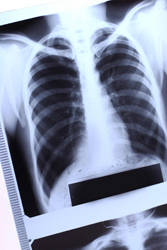

Tuberculosis rates are on the rise worldwide, with 8.8 million new cases and 2 million deaths being recorded each year. Better understanding the interactions between host and mycobacteria is vital for designing vaccination or immunotherapies.

Although some 90\;% of individuals infected with tuberculosis (TB) never develop clinical disease, the possible progression from infection to disease is not standard. Of those who are infected and do develop overt clinical disease, about 50\;% are diagnosed as fast progressors, being diagnosed with TB within 2 years of infection. The other half develop clinical disease later; such cases are described as 'reactivation' or post-primary TB. Immunisation with the Mycobacterium bovis–derived Bacillus Calmette-Guerin (BCG) vaccine can provide protection against childhood TB, but is relatively useless in protecting older children and adults from contracting the disease. Thus, infected individuals carry with them a life-long risk of reactivation, which is intensified when the immune system is weakened, as in the case of HIV infection. The 'Host and microbial molecular dissection of pathogenesis and immunity in tuberculosis' (HOMITB) project is investigating the interactions between mycobacteria and host cells. Since such interactions can lead to infection, examining their regulation by cellular immune responses is also a part of the study. Both targeted and genome-wide explorations are being employed to identify genes involved in the immunological control or development of primary Mycobacterium tuberculosis infection in children and secondary pulmonary TB in adults. HOMITB is also using various mouse models and human patients to investigate the role that key intracellular signalling molecules play in the immune response and outcomes of mycobacterial infection.